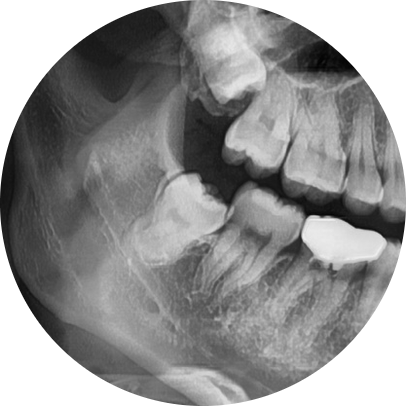

바른영치과 매복사랑니 발치사례

반대로 사랑니가 잘 자리를 잡고 났고, 구강청결 유지가 잘 이루어지기만 한다면 굳이 사랑니발치를 하실 필요는 없습니다. 그러나 아까 말씀드린 것처럼 사랑니가 일부 잇몸만 뚫고 나오는 비스듬시 자리하는 반매복 사랑니이거나 잇몸을 미처 뚫지 못해 잇몸 아래에서 자라고 있는 완전 매복 사랑니의 경우, 그리고 매복여부 상관없이 발치하는 것이 유리합니다.

단, 사랑니발치는 정상적으로 나지 않고 조금이라도 잇몸에 매복이 되어 있는 경우에는 잇몸절개 후 발치를 진행해야 하는데요. 하지만 잇몸에는 수많은 신경과 안면 감각기관이 모여 있어 난도 높은 치과진료 과목으로 손꼽힙니다. 때문에 옥수역치과 선택 시에는 사랑니발치 사례 경험이 많은 의료진이 있는지를 살펴보고 선택할 필요가 있습니다.

옥수역치과에서는 3D-CT를 통해 환자의 구강상태를 면밀히 살펴 사랑니의 매복 여부 및 형태 등을 확인한 후 적합한 치료방법을 통해 난도 높은 사랑니 발치를 도와드리고 있습니다. 또한 사랑니발치 시 부담을 느끼게 될 통증에 대한 두려움을 줄여드리기 위해 디지털 무통마취기 또한 구비해 두고 있습니다.